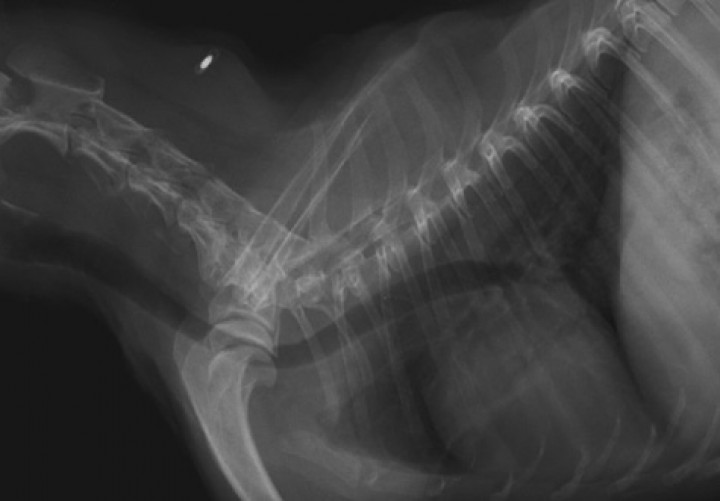

No se hallan anomalías radiográficas visibles a nivel de la cabeza ni de la región laríngea.

En la Fig. 3B se aprecia un diámetro traqueal homogéneo en todo su recorrido, tanto cervical como torácico, con una leve reducción del calibre intraluminal traqueal a la entrada del tórax, así como un desplazamiento ventral de la tráquea en esta localización (flecha azul). No se observan patologías mediastínicas/pleurales. El corazón y los grandes vasos no presentan alteraciones significativas, con ausencia de cardiomegalia y/o remodelación cardíaca. No se aprecian patrones pulmonares de interés.

Se recomendó un tratamiento conservador de reposo estricto durante 4 semanas con radiografía semanal de revisión, evitar periodos de estrés o anticiparse a estos con la administración de agentes sedantes y, además, evitar el uso de collar y arnés que comprimieran la zona de la tráquea. No se observaron signos clínicos, el paciente permanecía asintomático en la revisión a las 4 semanas y en la radiografía (Fig. 4) se observaba ausencia de herniación pulmonar y apariencia de la tráquea similar a la Fig. 2.

<p>Proyección latero-lateral derecha del tórax y la región cervical realizada a las 4 semanas tras el episodio inicial donde se observa una imagen traqueal compatible con la normalidad.</p>

Proyección latero-lateral derecha del tórax y la región cervical realizada a las 4 semanas tras el episodio inicial donde se observa una imagen traqueal compatible con la normalidad.